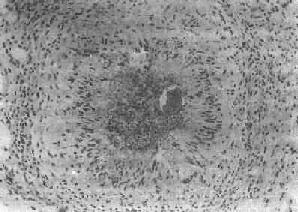

(1)急性虫卵结节:肉眼观为灰黄色、粟粒至绿豆大(0.5~4mm)的小结节。镜下见结节中央常有1~2个成熟虫卵,也偶可多达20个以上。这些成熟虫卵的卵壳上附有放射状嗜酸性的棒状体,也称为Hoeppli现象,用免疫荧光法已证实为抗原抗体复合物。虫卵周围是一片无结构的颗粒状坏死物质及大量嗜酸性粒细胞浸润。因其病变类似脓肿,故也称为嗜酸性脓肿(图19-5)。在坏死组织中可混杂多数菱形或多面形屈光性蛋白质晶体,即Charcot-Leyden结晶,系嗜酸性粒细胞的嗜酸性颗粒互相融合而成。随后虫卵周围产生肉芽组织层,其中有以嗜酸性粒细胞为主的炎症细胞浸润,还有单核巨噬细胞、淋巴细胞、浆细胞及少量中性粒细胞。随着病程的发展,肉芽组织层逐渐向虫卵结节中央生长,并出现围绕结节呈放射状排列的类上皮细胞层。类上皮细胞层逐渐加宽,嗜酸性粒细胞显著减少,构成晚期急性虫卵结节(图19-6),这是向慢性虫卵结节发展的过渡阶段。

图19-5 肝血吸虫病之急性虫卵结节

结节中心有一成熟虫卵,卵壳表面可见放射状物质,周围广泛坏死伴大量嗜酸性粒细胞浸润